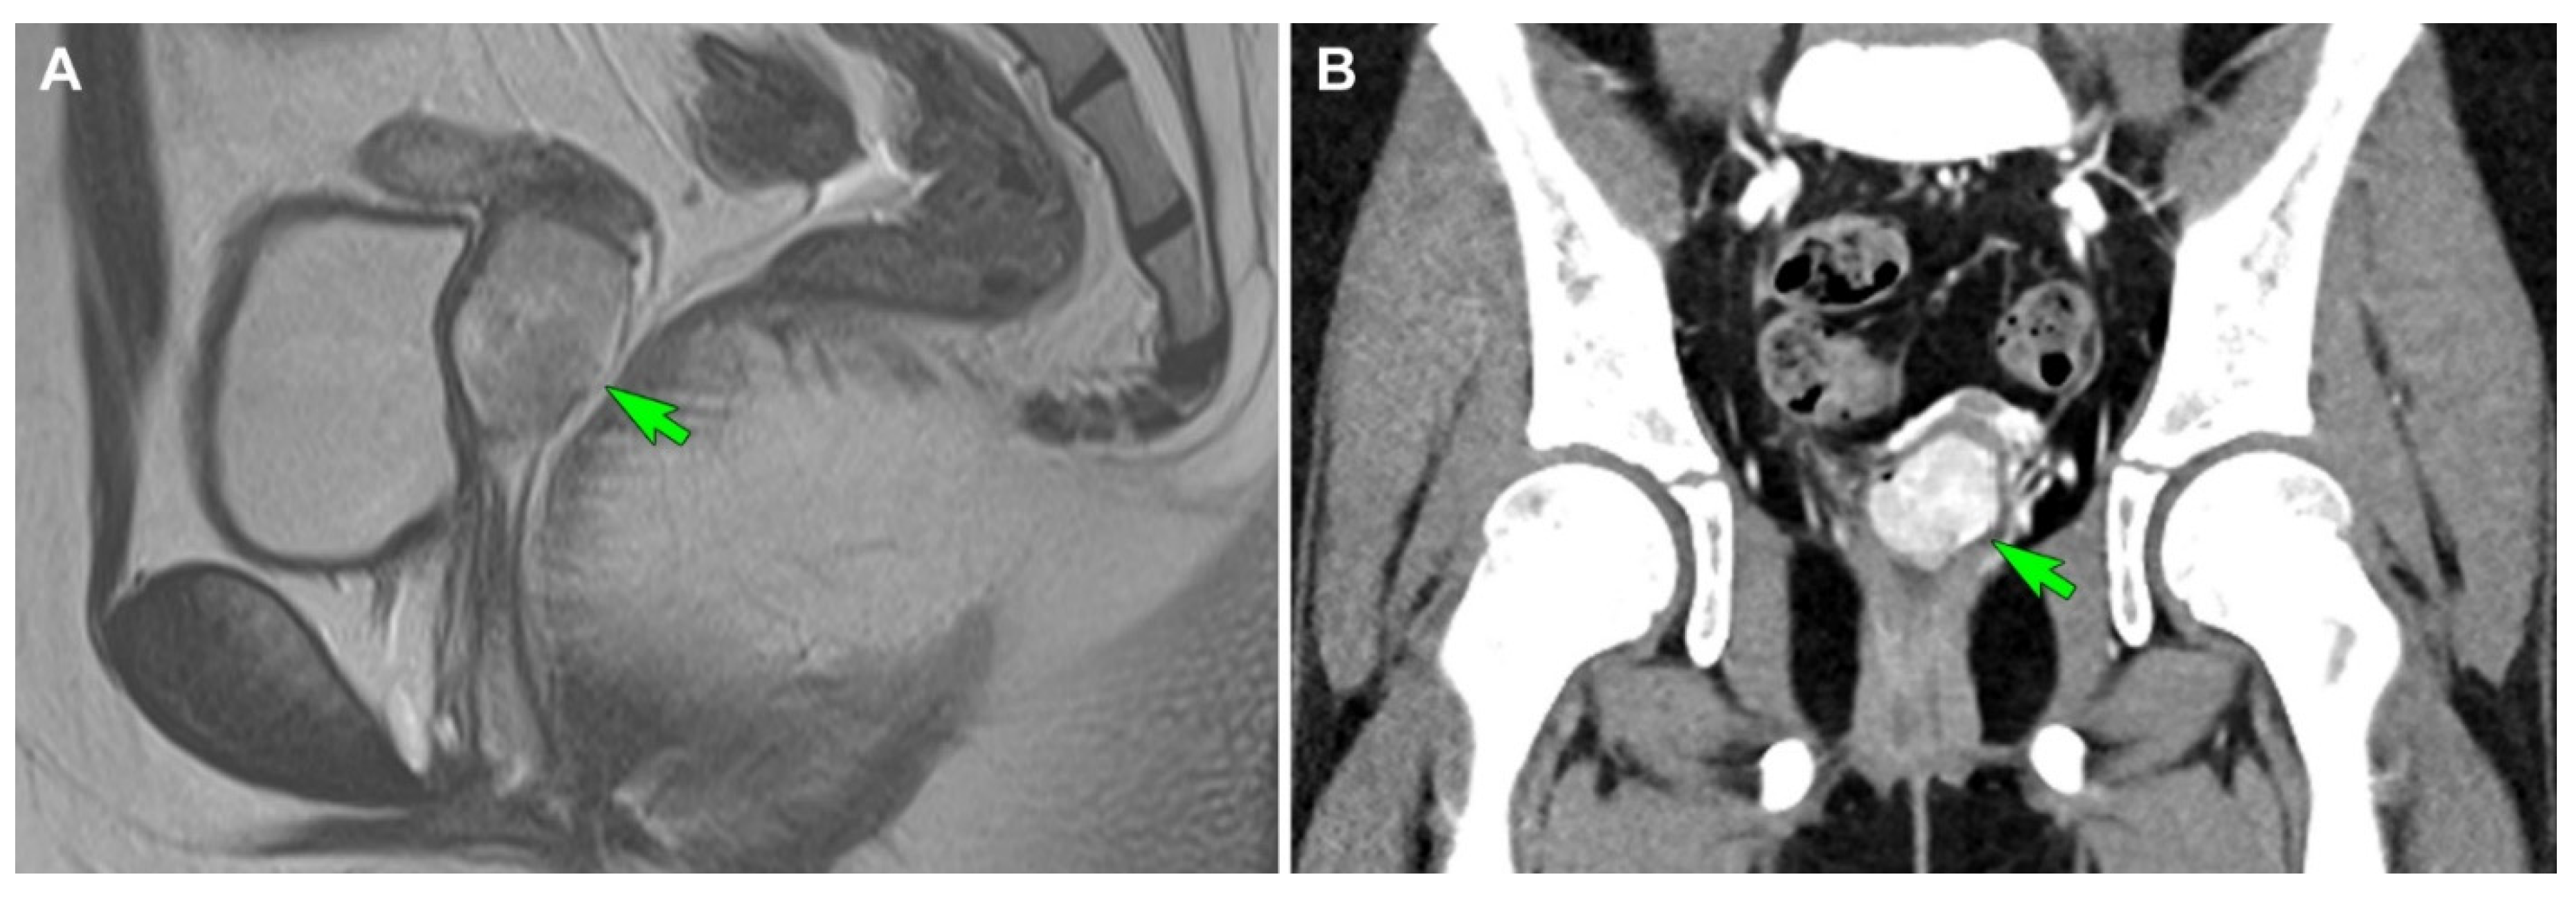

3.2.1. Clinical Presentation

3.2.2. Pathological Findings